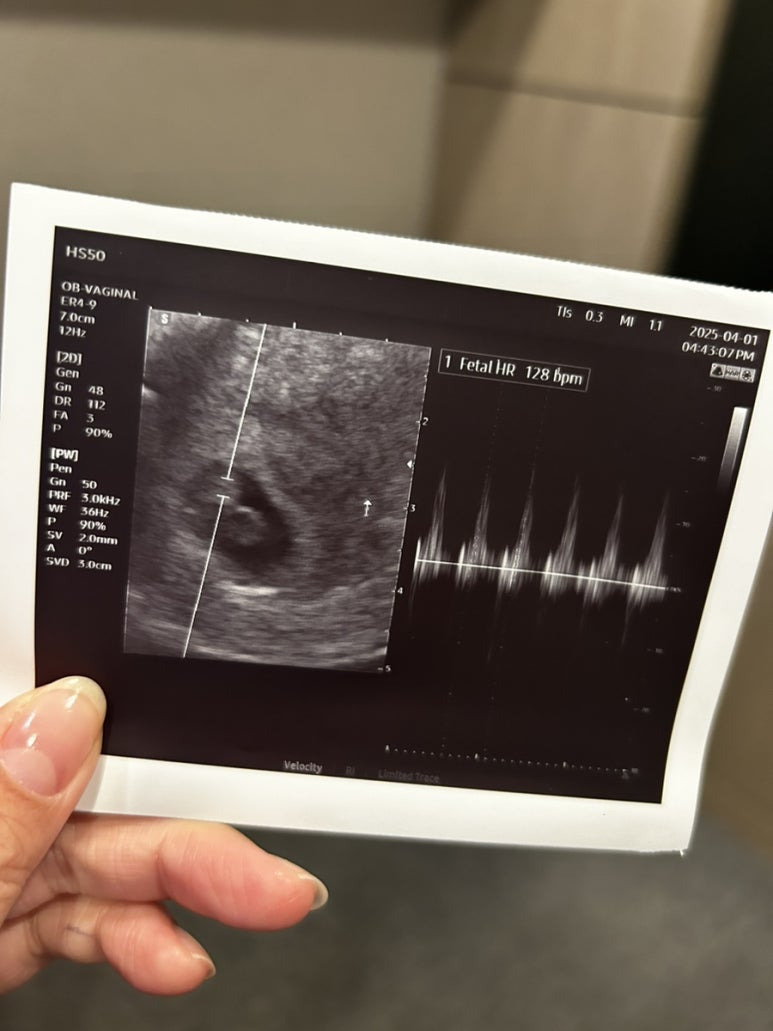

그리고 처음 들은 사탕이 심장소리

128bpm 으로 잘 뛰고있었다.